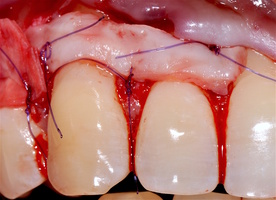

1. Генерализованные рецессии в области нижней челюсти оперировались в один этап все 12 зубов, фронтальный участок с аутотрансплантатом от 3.2 до 4.2 зубов. А дистальные участки от 3.6 до 3.3 и от 4.6 до 4.3 зубов с использованием пластического материала ТМО (dura mater) (рис. 4а-з).

4. Этапы хирургического лечения рецессий десны на нижней челюсти

3.2-4.2 зубы были прооперированы методом, сочетающим вестибулопластику с одновременным увеличением ширины и толщины прикрепленной десны при помощи свободного десневого аутотрансплантата (операция Bjorn, 1963 г.).

5. Хирургическая методика

1. Подготовка принимающего ложа. Включает в себя формирование полнослойно-расщепленного слизисто-надкостничного лоскута (полнослойного в области зенитов рецессий, расщепленного билатерально области рецессии десны), рассечение и отслаивание слизисто-мышечных волокон вестибулярно ниже мукогингивальной границы, деэпителизация межзубных сосочков.

2. Обработка поверхностей корней зубов. Включает ультразвуковую обработку скейлером для очищения от минерализованных зубных отложений и мягкого зубного налета, экспозицию геля ЭДТА 17% в течение двух минут, механическое удаление слоя бесклеточного цемента импрегнированного микроорганизмами зоноспецифическими кюретами, полировку пародонтологическими борами («фасолька» и «обратный треугольник»).

3. Получение аутотрансплантата: начинается с определения толщины донорской зоны и замеров размера будущего трансплантата. Зона забора от второго премоляра до третьего моляра верхней челюсти. Глубина погружения брюшка скальпеля 2 мм, далее трансплантат оптимизируют — деэпителизируют по периметру.

4. Затем проводиться позиционирование аутотрансплантата в области рецессий и принимающего ложа двумя-тремя узловыми швами; после аутотрансплантат стабилизируют прижимающими двумя-четырьмя матрасными крестообразными швами, что позволит плотно прижать аутотрансплантат и избежать образования «мертвых» зон для питания аутотрансплантата.